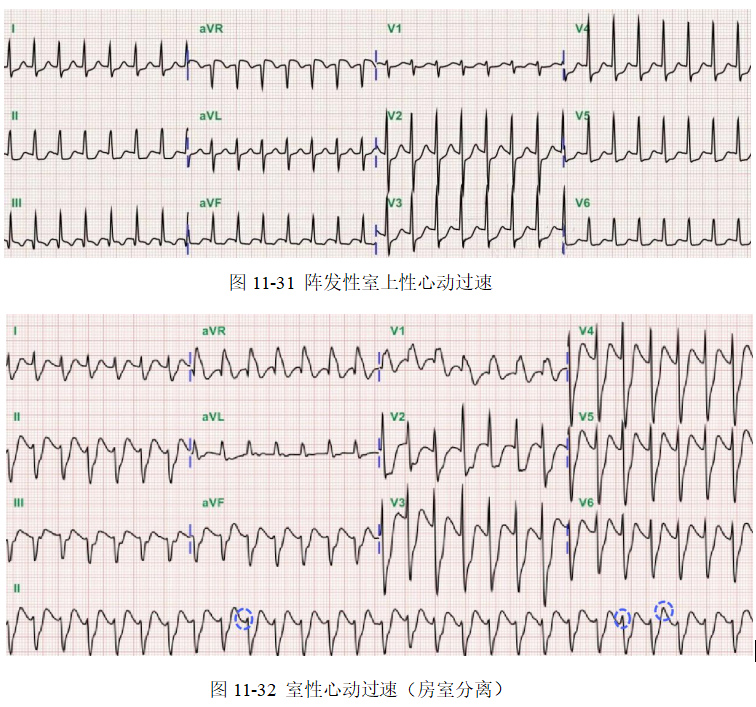

1.阵发性室上性心动过速(paroxysmalsupraventriculartachycardia)理应分为房性以及与房室交界区相关的心动过速,但常因P'不易辨别,故统称为室上性心动过速(室上速)。该类心动过速发作时有突发、突止的特点,频率一般在160~250次/分,节律快而规则,QRS形态一般正常(伴有束支阻滞或室内差异性传导时,可呈宽QRS波心动过速)。临床上最常见的室上速类型为预激旁路引发的房室折返性心动过速(AVRT)以及房室结双径路(dualA-Vnodalpathways)引发的房室结折返性心动过速(A-Vnodalreentrytachycardia,AVNRT)。心动过速通常可由一个房性期前收缩诱发。这两类心动过速病人多不具有器质性心脏病,由于解剖学定位比较明确,可通过导管射频消融术根治。房性心动过速包括自律性和房内折返性心动过速两种类型,多发生于器质性心脏病基础上。

2.室性心动过速(ventriculartachycardia)室性心动过速属于宽QRS波心动过速类型,心电图表现为:①频率多在140~200次/分,节律可稍不齐;②QRS波群形态宽大畸形,时限通常>0.12秒;③如能发现P波,并且P波频率慢于QRS波频率,PR无固定关系(房室分离),则可明确诊断;④偶尔心房激动夺获心室或发生室性融合波,也支持室性心动过速的诊断。